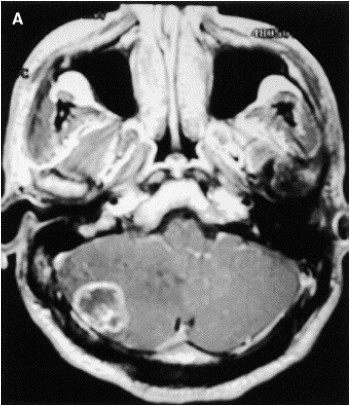

Considere um paciente masculino 55 anos com historia de hemiparesia direita há 2 semanas, sem nenhum fato significante de antecedente.

De acordo com a imagem acima, dentre os diagnósticos abaixo descritos, qual o mais provável?